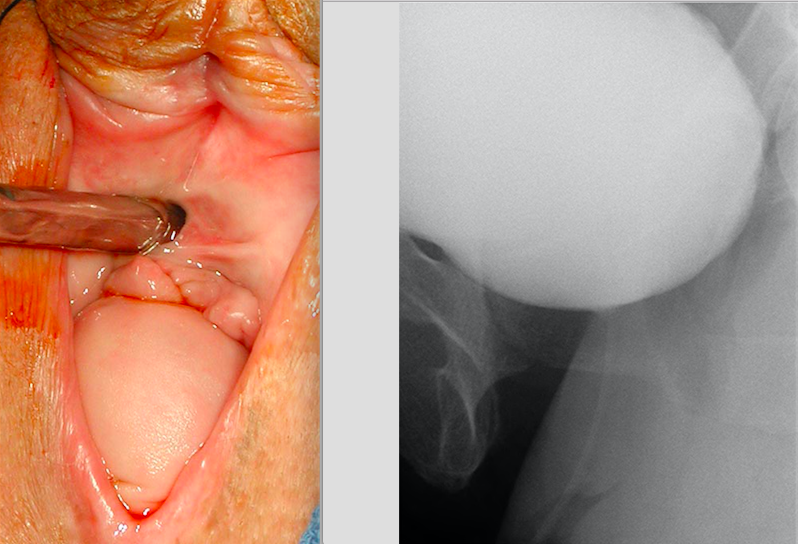

A 55-year-old active woman desires surgical repair of a vaginal bulge. She has urinary frequency but no urinary or fecal incontinence. The physical examination with a cystoscope in the urethra is shown followed by a cystogram at maximal Valsalva taken during a videourodynamic study. The next step is:

5

This patient has vaginal vault prolapse. The image from the videourodynamics study does not demonstrate a cystocele. The majority of physicians would recommend that this patient should undergo repair of the vault prolapse with a concurrent anti-incontinence procedure. The concurrent anti-incontinence procedure is performed due to the increased risk of de novo stress incontinence following vault suspension. In the context of a robotic sacrocolpopexy, a midurethral sling would be the most appropriate approach. Urodynamics, with or without prolapse reduction, are not predictive of which patients will develop de novo SUI following vault suspension. While acceptable to proceed with robotic sacrocolpopexy and no sling, the patient should be informed of the risk of postoperative stress incontinence. Some patients may prefer this approach due to the inherent risks of sling procedure, however rare they may be.